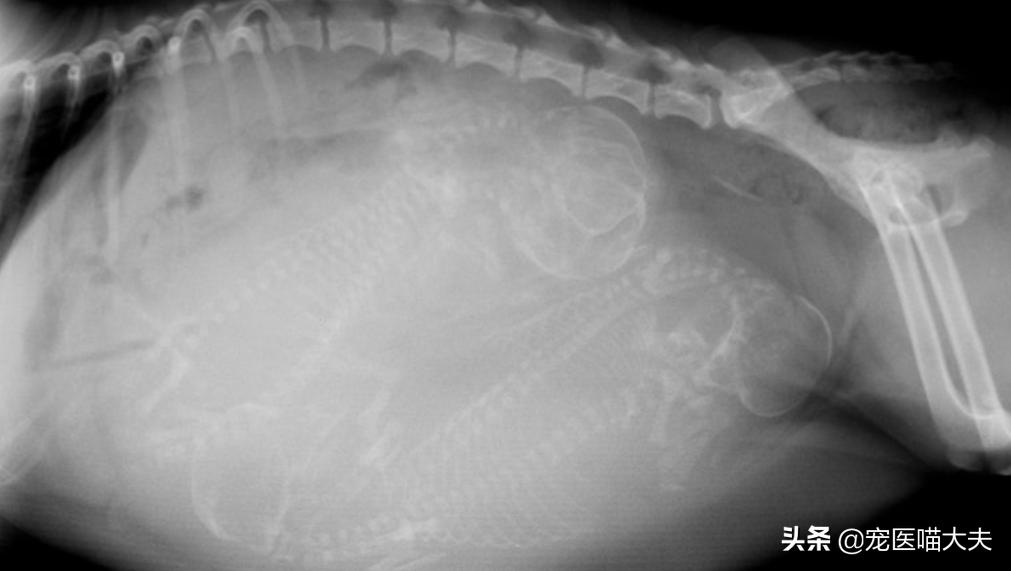

X射线检查一般用在雌性狗狗的怀孕后期,通过X射线检查,可以大约判断出狗妈妈子宫内小狗的数量;一般在55天之后进行X射线检查才可以准确判断出小狗的数量,因为在其之前,胎儿的颅骨和脊柱正在发育,且在X片上不可见,所以,对狗狗进行X射线检查时,掌握时间是非常重要的哦;另外,通过X射线检查也可判断狗狗是否有胎儿性难产或母体性难产的风险,比如胎儿是否过大和狗妈妈盆骨是否过窄等。

X射线检查怀孕的狗狗